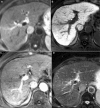

Hepatocellular carcinoma (HCC) is one of the most common primary hepatic malignancies and one of the fastest-growing causes of cancer-related mortality in the United States. The molecular basis of HCC carcinogenesis has not been clearly identified. Among the molecular signaling pathways implicated in the pathogenesis of HCC, the Wnt/β-catenin signaling pathway is one of the most frequently activated. A great effort is under way to clearly understand the role of this pathway in the pathogenesis of HCC and its role in the transition from chronic liver diseases, including viral hepatitis, to hepatocellular adenomas (HCAs) and HCCs and its targetability in novel therapies. In this article, we review the role of the β-catenin pathway in hepatocarcinogenesis and progression from chronic inflammation to HCC, the novel potential treatments targeting the pathway and its prognostic role in HCC patients, as well as the imaging features of HCC and their association with aberrant activation of the pathway.